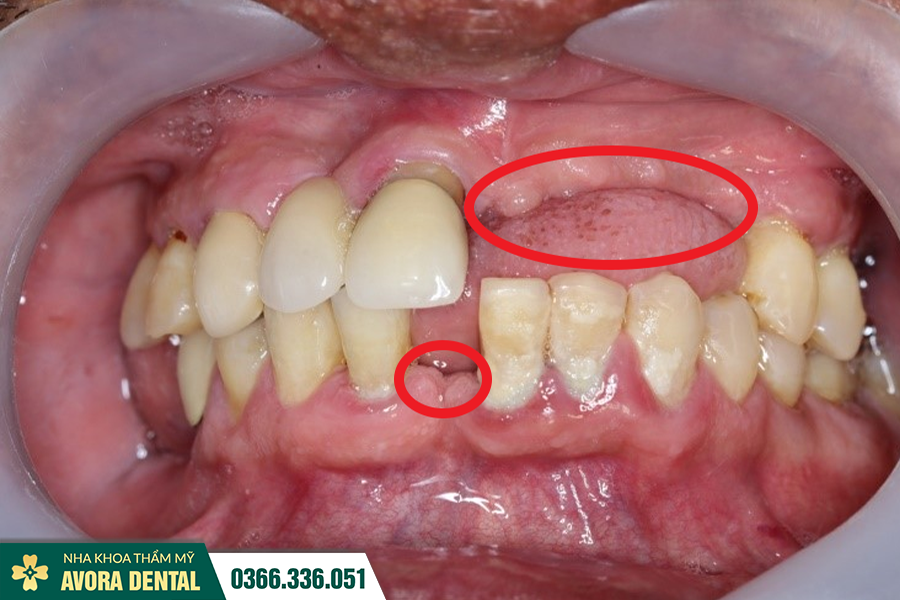

Trải nghiệm khách hàng trước và sau khi sử dụng dịch vụ

Mỗi khách hàng khi đến với Nha khoa AVORA Dental đều được thiết kế lộ trình cá nhân hóa, đảm bảo mang lại hiệu quả tối ưu. Những hình ảnh trước và sau khi phục hình răng tại nha khoa đã làm cho nhiều khách hàng phải bất ngờ. Không chỉ cải thiện sức khỏe răng miệng mà còn tôn lên vẻ đẹp tự nhiên của nụ cười.